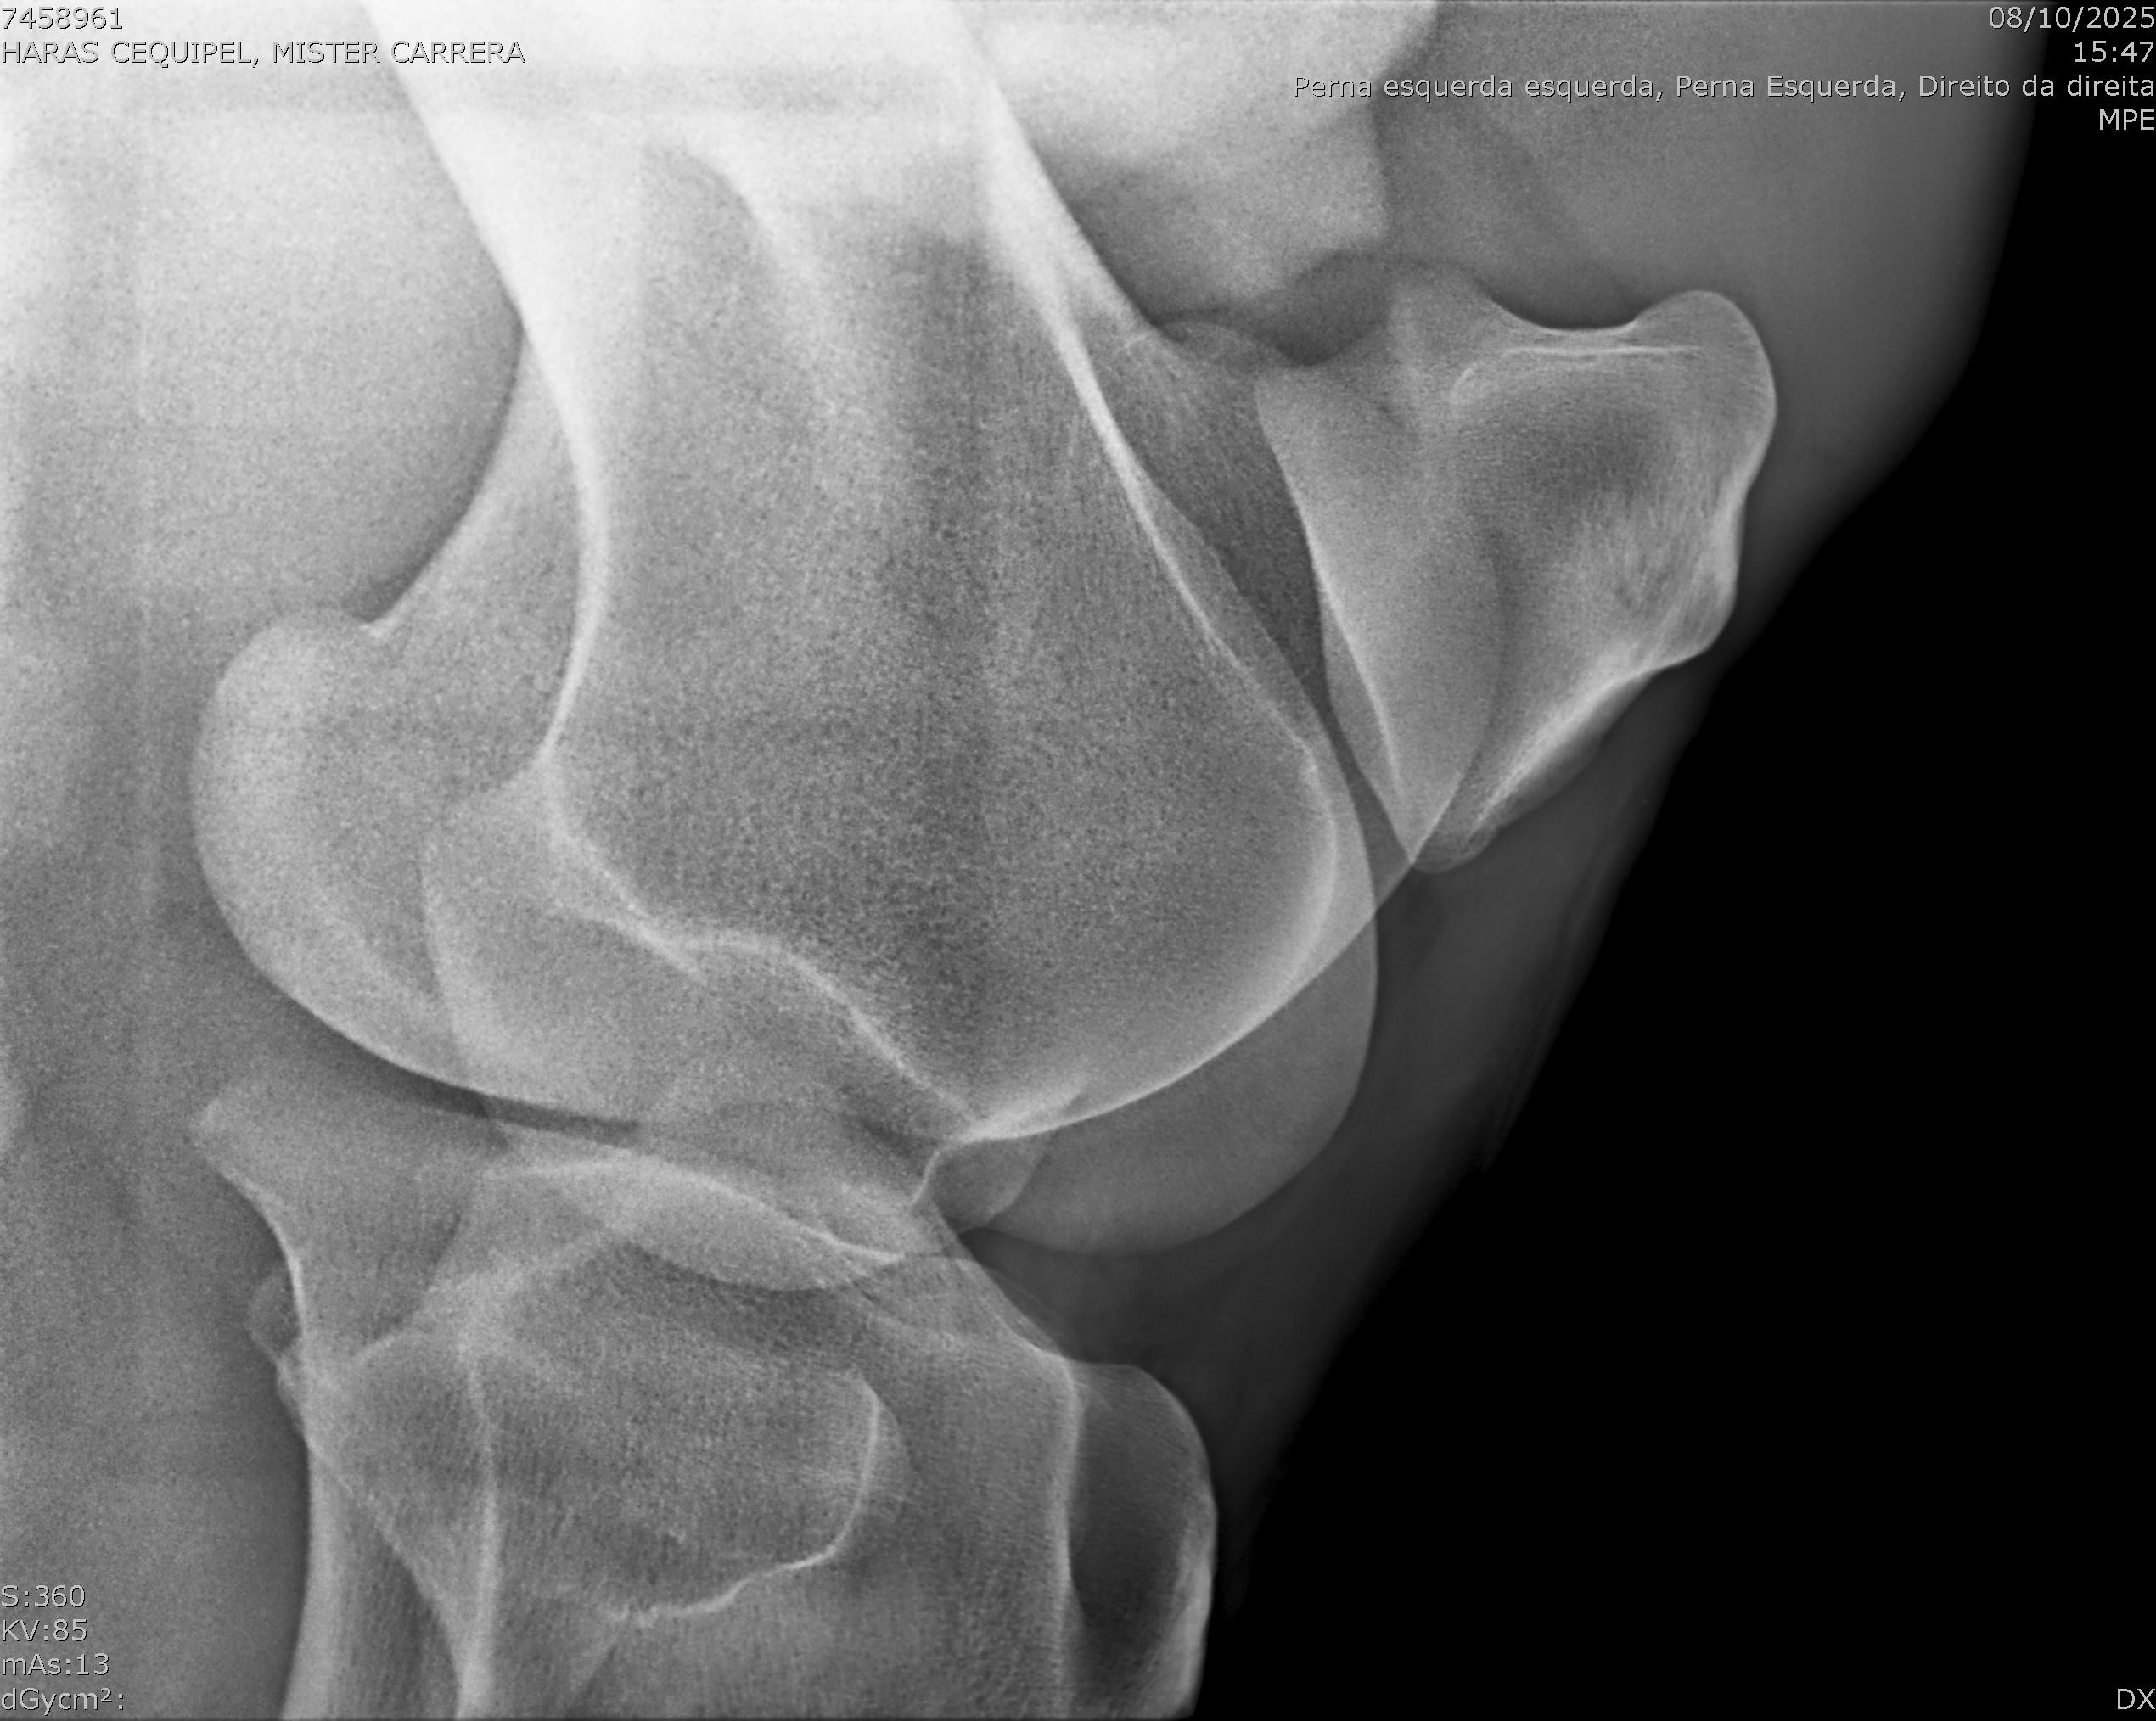

:: RAIOS-X DO LOTE